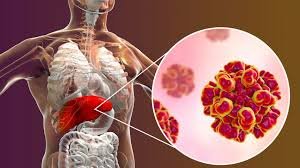

डेस्क: फैटी लिवर एक साइलेंट डिजीज है, जो धीरे-धीरे शरीर को नुकसान पहुंचाती है। अक्सर इसके शुरुआती लक्षण पेट से शुरू…

फैटी लिवर सुनने में भले ही हल्की समस्या लगे, लेकिन हकीकत इससे कहीं ज्यादा खतरनाक है. यह बीमारी धीरे-धीरे लिवर…